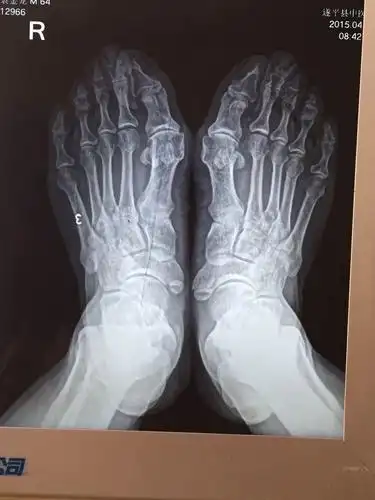

拇外翻大脚骨手术矫治术

x光片更直观了解大脚骨 如果单纯去掉凸起能否有效矫正拇外翻呢?

拇外翻俗称大脚骨的微创无痛美容矫正术